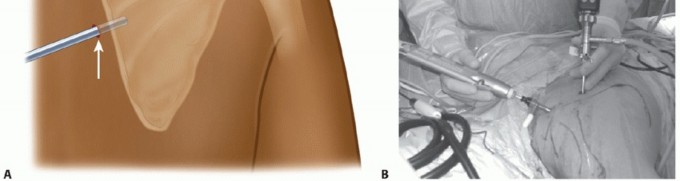

The patient is positioned in the prone position for both arthroscopic and open techniques (FIG 5).

The involved arm is placed in internal rotation against the patient's lower back (chicken wing position). This will cause the scapula to wing out from the thorax and make the superomedial angle more prominent.

FIG 5 • The operating room setup for arthroscopic scapulothoracic bursectomy. The patient is positioned prone with the hand of the involved shoulder placed behind the back in order to lift the scapula off the chest wall.*

The surgeon stands on the side opposite the scapula to be operated to get the best access to the surgical field.

FIG 5 • The operating room setup for arthroscopic scapulothoracic bursectomy. The patient is positioned prone with the hand of the involved shoulder placed behind the back in order to lift the scapula off the chest wall.*

The surgeon stands on the side opposite the scapula to be operated to get the best access to the surgical field.